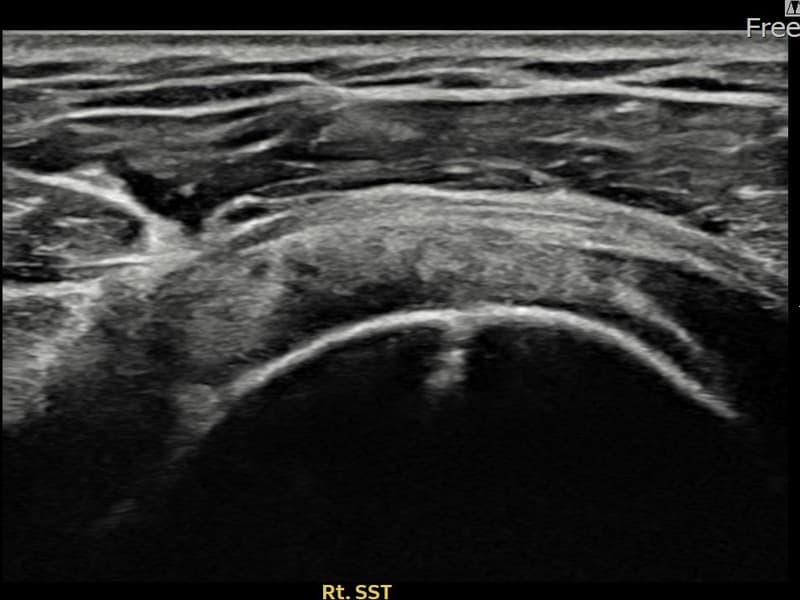

After

시술 전 초음파 측정 결과 파열 크기는 9mm × 4mm (힘줄 두께의 약 38% 결손)로 확인되었습니다. 시술 전 초음파에서 우측 극상근건 관절면측의 에코 단절과 힘줄 내 저에코 결손 소견이 확인되었습니다. 시술 후 초음파에서 파열 부위가 재생 조직으로 채워지고 힘줄 연속성이 회복된 것이 관찰되었습니다.

50대 초반 남성 환자분으로, 우측 어깨 통증이 1년 이상 지속되었으나 바쁜 일상으로 치료를 미루시다 내원하셨습니다. 팔을 90도 이상 들어 올릴 때 통증이 심하고 야간 통증으로 옆으로 눕지 못하는 상태였습니다. 초음파 검사에서 관절면측 극상근건 부분파열이 확인되었으며, 수술 없이 초음파 유도 하 축소봉합술을 시행하였습니다. 시술 후 보조기 착용과 단계적 재활을 통해 진행하였고, 시술 13주 후 추적 초음파에서 파열 부위의 구조적 회복이 확인되어 정상 업무에 복귀하셨습니다.